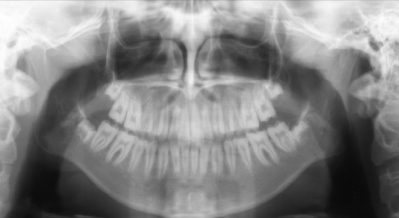

15 歳の女子。飲水時の上顎臼歯部における疼痛を主訴として来院した。歯の表面性状は萌出してから変化はないという。皮膚に異常は認められない。初診時の口腔内写真とエックス線画像を別に示す。

診断名はどれか。1つ選べ。

d. エナメル質形成不全症